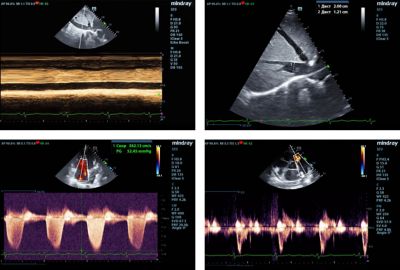

Two-dimensional transthoracic echocardiography was performed on a Mindray M9 ultrasound machine using monocrystal sector SP5-1s transducer. The examination revealed a 20 mm thick hyperechoic mass in the left ventricular (LV) cavity, closely associated with the inferior and inferolateral segments of the LV myocardium. This mass involved the posteromedial papillary muscle, posterior mitral valve leaflet and caused moderate mitral regurgitation. (Figure 1,2).

Fig. 1 - Hyperechoic mass in the LV cavity involving myocardium, papillary muscle and posterior mitral valve leaflet.

Fig. 2 - Mitral and tricuspid regurgitations.

A slight dilatation of both atria, moderate tricuspid regurgitation, overload, and decreased contractility of the right ventricle (TAPSE = 12), moderate pulmonary hypertension (Figure 3), and restrictive transmitral blood flow (Figure 4) were also detected. LV ejection fraction (EF) was preserved (65%).

Fig. 3 - The echocardiography patterns of pulmonary hypertension.

Fig. 4 - The restrictive pattern of trans-mitral flow.